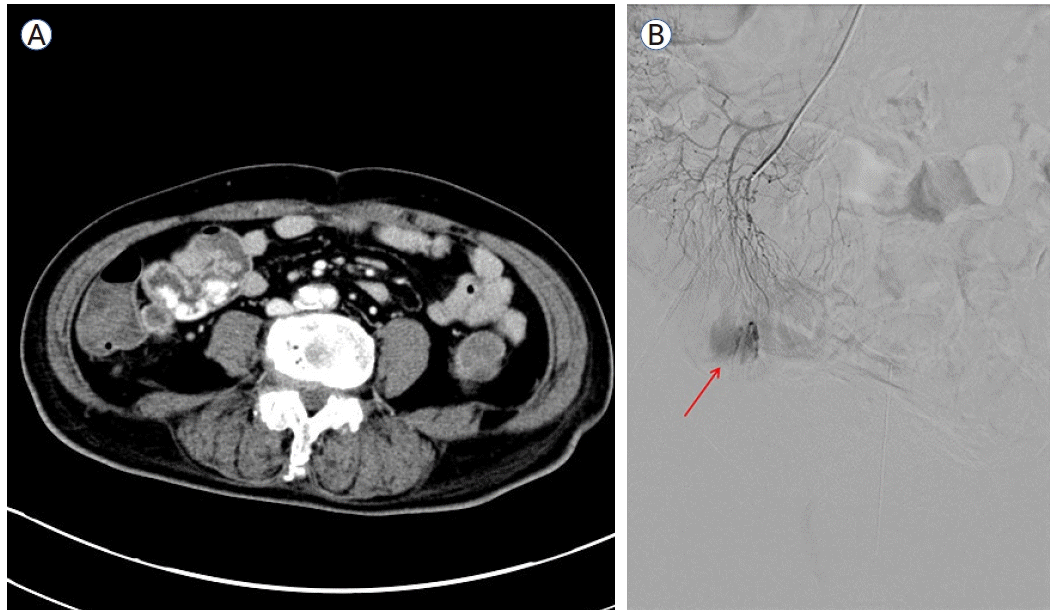

수술 중 병변의 위치를 찾기 위하여 병변으로 의심되는 부위에 클립을 결찰한 후 코일과의 상대적인 위치를 C-arm을 통해 확인하여 보정하는 과정을 거쳤다. 회결장동맥(ileocolic vessel)을 결찰한 뒤 장간막동맥(mesenteric branch)에 위치한 코일이 확인되었고(Fig. 4) C-arm을 통해 코일의 위치를 재확인하여 병변의 위치를 특정하였다. 리가슈어(LigaSureTM; Medtronic, Minneapolis, MN, USA)로 장간막을 나눈 후 장간막 반대편 경계를 따라 말단 회장 근처의 소장 절제술을 시행하였다(Fig. 5A). 절제된 소장 부위에서 궤양성 병변이 확인되어 소장을 봉합한 후 수술을 마무리하였다.

Figure 4.

Fluoroscopic location of the embolization coil. A radiograph of the pathologic specimen showed the presence of the microcoil within the ileal arterial branch.